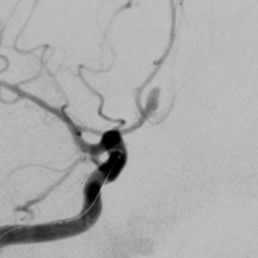

Most occur at branching points of the arteries (so-called ‘saccular’ or ‘berry aneurysms’).

More rarely they involve the entire segment of an artery, called a ‘fusiform aneurysm’.

Two main treatment options exist: Endovascular coiling of aneurysms (where a catheter is inserted through arteries under x-ray guidance and tiny platinum based coils are placed inside the aneurysm), and open surgical clipping of aneurysms.

Both treatments are successful at treating aneurysms. Which is best depends on the shape, size and position of the aneurysm.